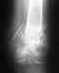

Re: Рентгенограмма переломов голени ч/з 34 дня после операции.

послал Дмитрий 24 Февраль 2009, 17:51

(В верхней части есть блокирующий винт, просто до него не хватило снимка)